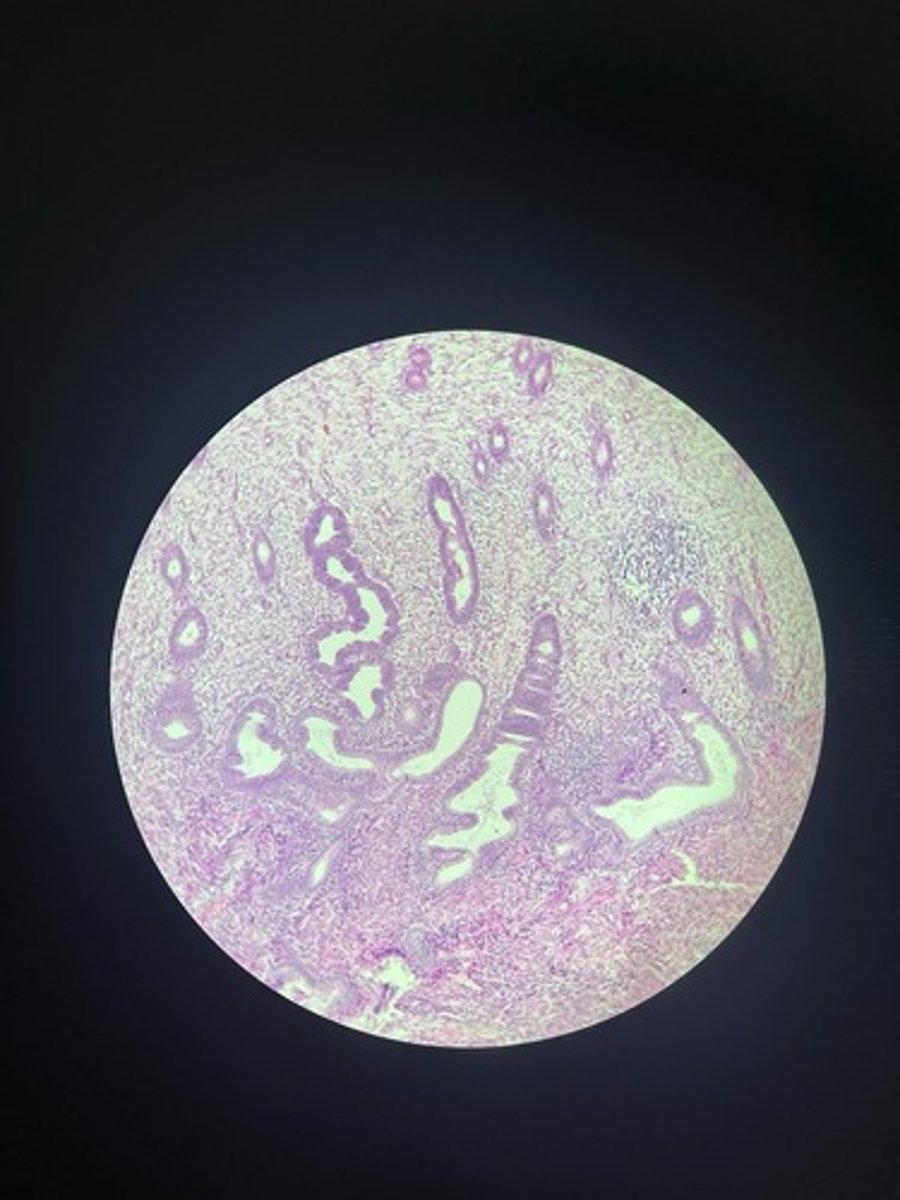

Prostate HE

Prostate HE

Prostate HE

Prostate HE